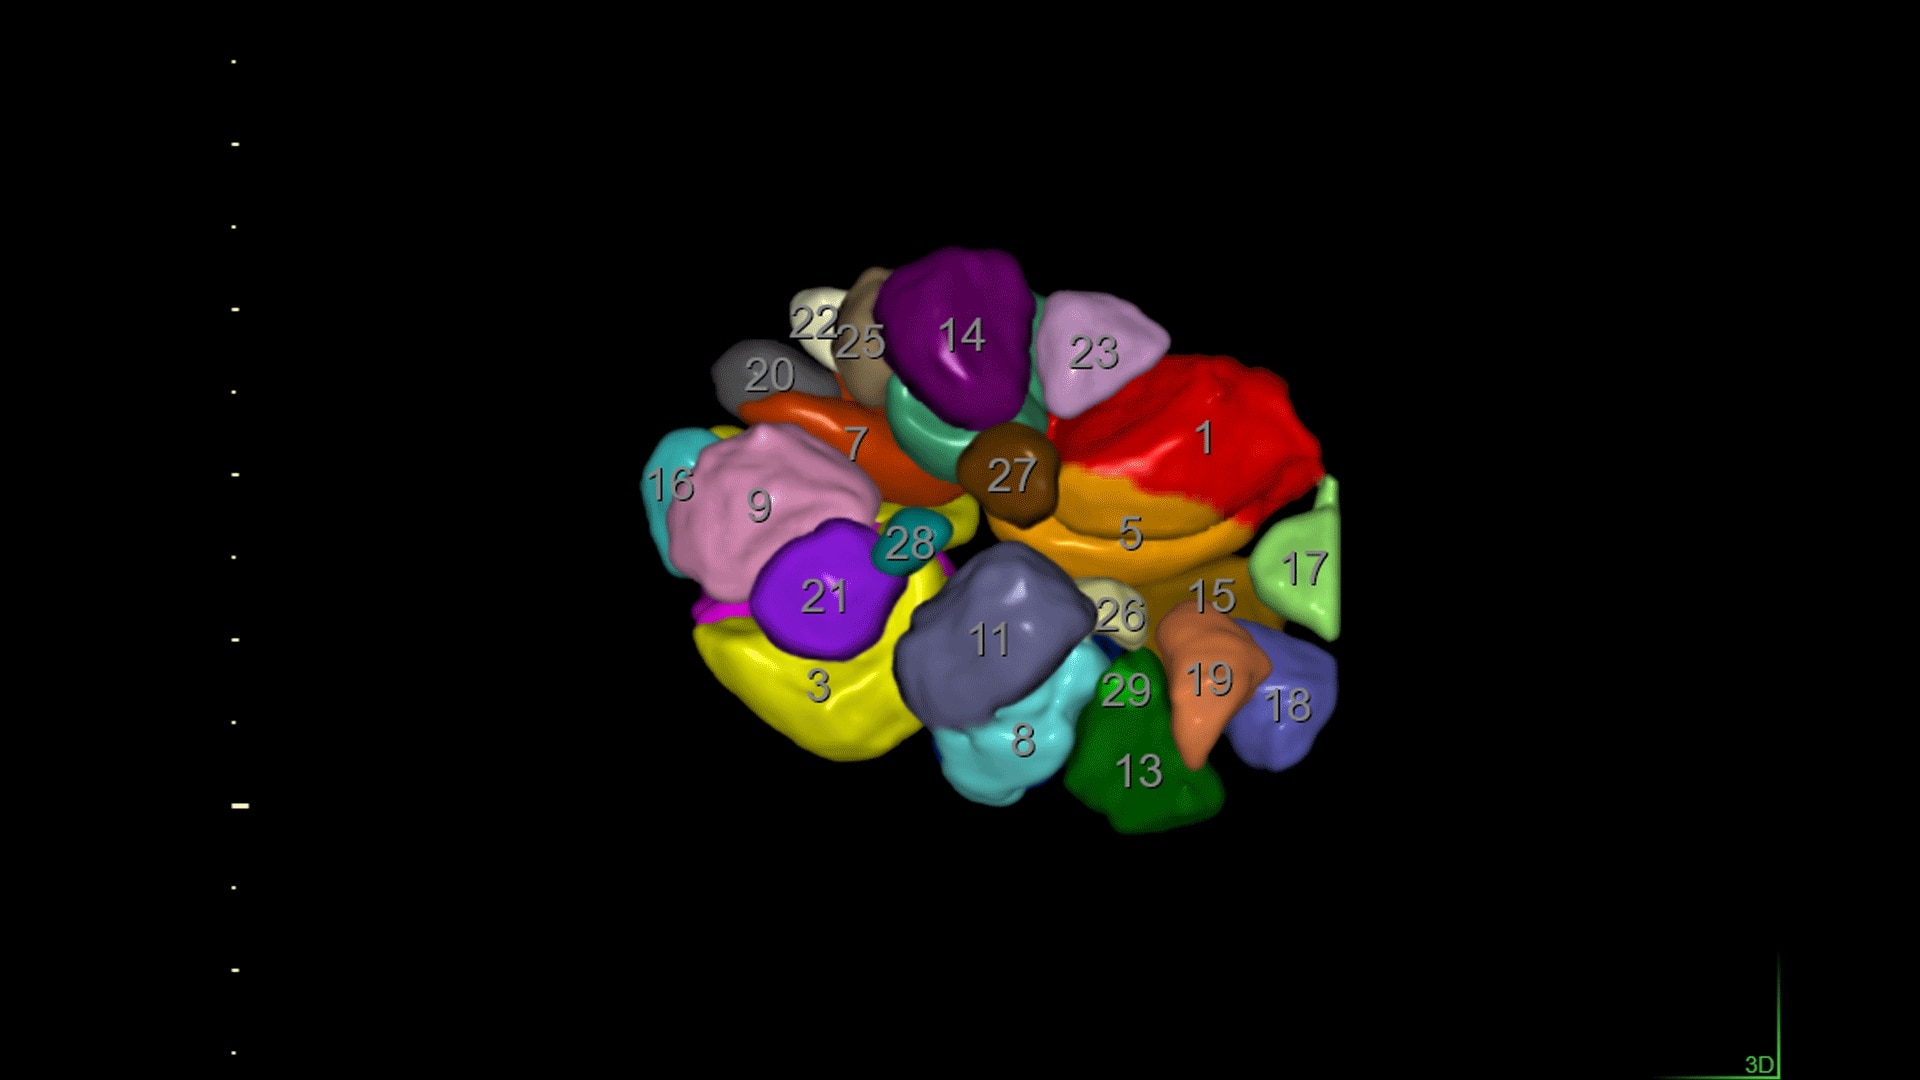

Practical, Easy 3D

With 3D features like SonoRenderlive, easily acquire fetal faces and use OmniView to obtain views not accessible with 2D. For another anatomical perspective add HDlive™.

SonoAVC™follicle

SonoAVC™follicle automatically calculates the number, dimensions, and volume of hypoechoic structures in a volume sweep to help monitor patient follicles faster.